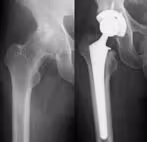

①高位脱臼性股関節症

脱臼している股関節を原臼位(元の位置)に再建するために大腿骨の短縮骨きりを同時に行い人工股関節を設置します。